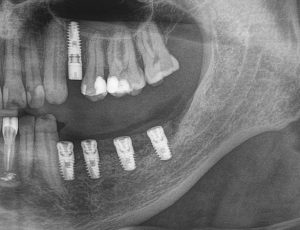

После операции мы делаем контрольные снимки. Это может быть ортопантомография:

или конусно-лучевая компьютерная томография. Как вам больше нравится.

Результат остеопластики методом остетотомии мы можем оценить уже через 4 месяца. Перед этим сделаем контрольные снимки (слева «до», справа «через 4 мес»):